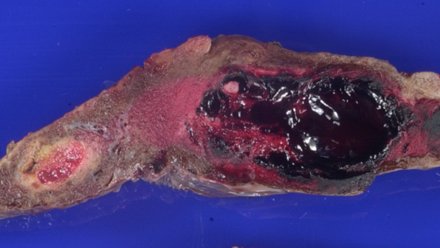

⁉️#GUpath #PEDIpath⚠️ 15YOB with a 7 mm intra testicular nodule... 🔪GROSS🔪 Woo Cheal Cho, MD GU Pathology Society (GUPS) Dr.Gauri Vidolkar MD Frank Ingram, MD Ankur Sangoi @evacomperat Daniel Skipper @AkgulMd Jonathan Zuckerman MD PhD Carla Ellis MD, MS Erasistrate Farshid Siadat, MD, FRCPC Francesca Khani, MD Peter Sadow, MD, PhD Ashish M. Kamat, MD, MBBS Nature Reviews Urology ⏭